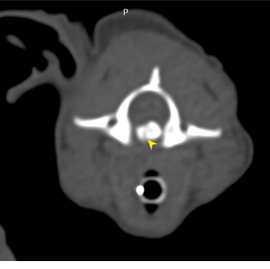

狗狗 頸椎骨折 電腦斷層影像科

四肢無力的狗狗經由神經學檢查 懷疑c5以上神經損傷,但xray無法診斷的時候

就需要仰賴電腦斷層掃描評估受傷位置及嚴重程度